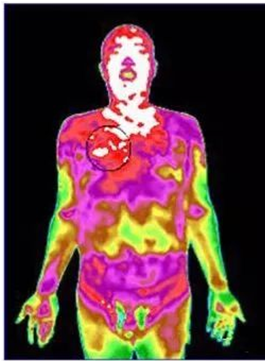

图2 甲状腺结节红外热成像图

图4 阳虚体质红外热成像图